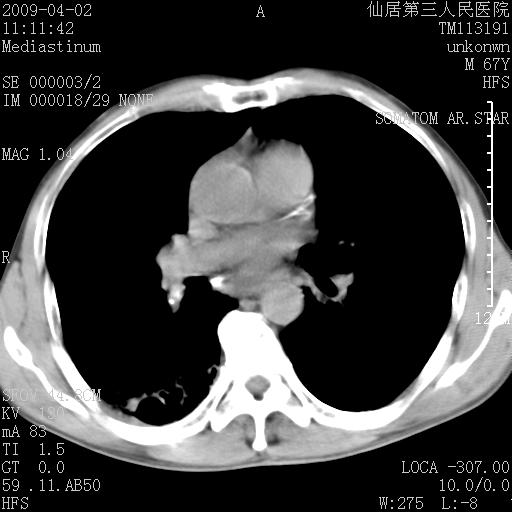

患者老年男性,乏力畏寒来诊,摄胸片示右下肺感染性病变,抗炎两周后复查胸片,无好转有进展。

后做ct平扫表现如下:

考虑右肺炎症可能性大,不除外细支气管肺泡癌

是否还要考虑肺间质纤维化,建议hrct扫描。

病灶呈蜂窝征,纵隔多个淋巴结肿大;肺泡癌需考虑

右肺下叶背段干酪性肺炎。请痰检[emb28]

我认为普通的感染应该可以除外,间质性肺炎可能性较大,但如何解释纵膈的淋巴结肿大呢

考虑双肺间质性改变(间质纤维化?)伴右肺下叶感染。